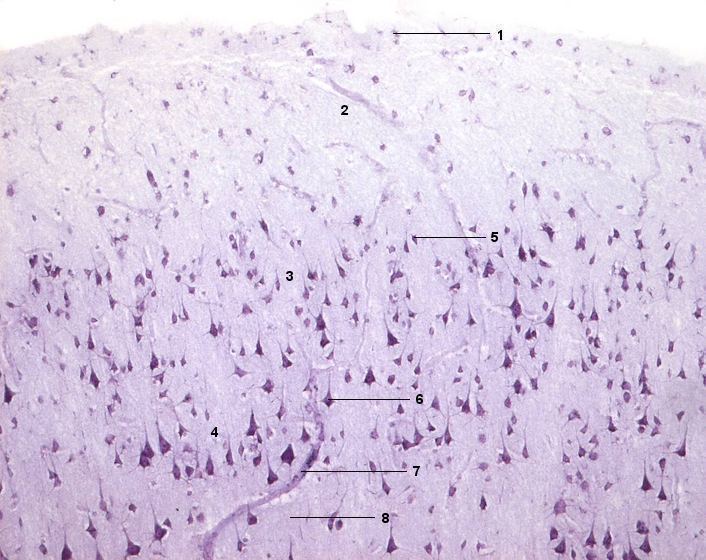

1 Membrana limitans gliae superficialis

2 Lamina molecularis

3 Lamina granularis externa

4 Lamina pyramidalis externa

5 Körnerzelle

6 Pyramidenzelle

7 Blutgefäß

8 Neuropil